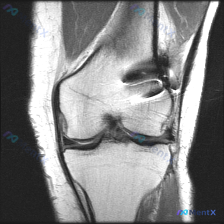

分享一个非常容易踩坑的膝关节MRI读片病例,整理了完整分析思路跟大家一起讨论。 病例影像基本信息 这是一份膝关节MRI T2序列冠状位影像,核心疑问是「观察到Meniscal abnormality(半月板异常)」,我们来一步步拆解分析。 系统阅片结果 按照解剖结构逐一评估: 1. 骨骼关节:股骨远...